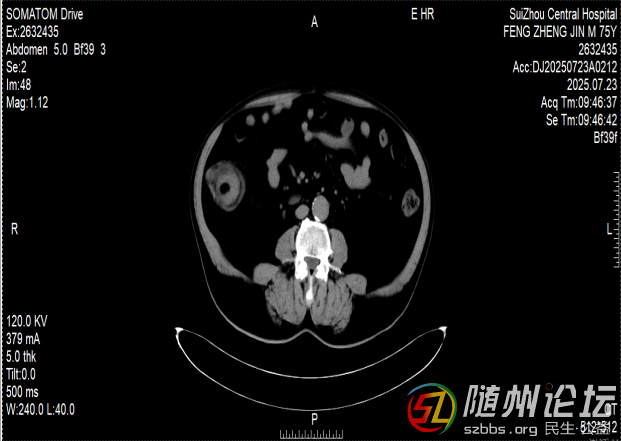

一位76歲的患者,近半年來飽受排便困難的折磨,輾轉(zhuǎn)多家醫(yī)院后,最終在隨州市中心醫(yī)院找到了病因——他的小腸末端,藏著一個直徑達6厘米的巨大腫瘤。

這個腫瘤就像一顆“定時炸彈”,已多次引發(fā)腸梗阻和腸套疊,導致老人無法正常進食,痛苦不堪。由于年事已高,傳統(tǒng)的開腹手術(shù)創(chuàng)傷大、恢復慢,家屬顧慮重重。

兩難之際,老人在家屬的陪同下找到了隨州市中心醫(yī)院消化內(nèi)鏡中心主任陳志勇。仔細評估病情后,陳志勇認為,盡管腫瘤巨大、位置特殊,手術(shù)風險很高,但仍有希望通過內(nèi)鏡微創(chuàng)切除,讓患者避免開腹之痛。